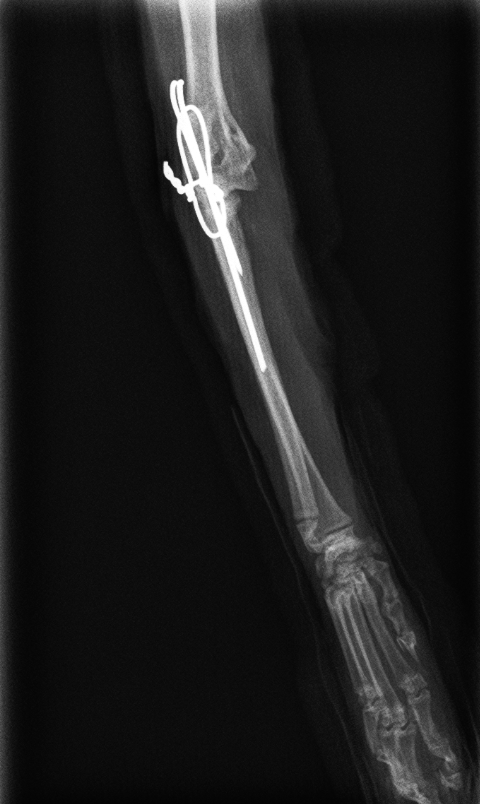

左肘頭骨折と診断し、髄内ピンとサークラージワイヤーによるテンションバンドにより固定した

after